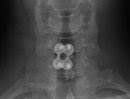

So in early October 2009 the Dr successfully completed an Anterior cervical discectomy and fusion (ACDF). Which is another topic for a later time.

The result of my surgery was a complete success, I now have about 97% feeling back in my hand and no muscle spasms. As for an additional bonus, now I have a Titanium plate & four titanium screws placed on my spine.